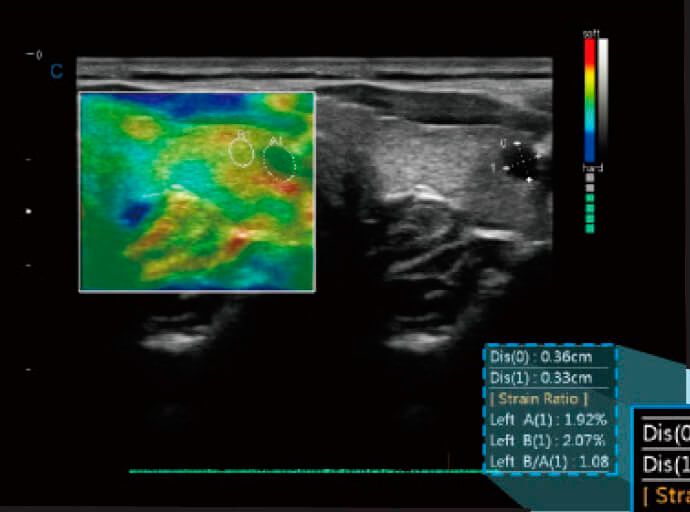

Élastographie quantitative

- Visualisez l'élasticité de différents tissus de différentes couleurs.

- Fournit de meilleures informations cliniques, en particulier sur les tissus mous.

- Mesure le rapport de contrainte quantitatif, fournissant le rapport entre la répartition des contraintes de la région sélectionnée et la région normale adjacente.